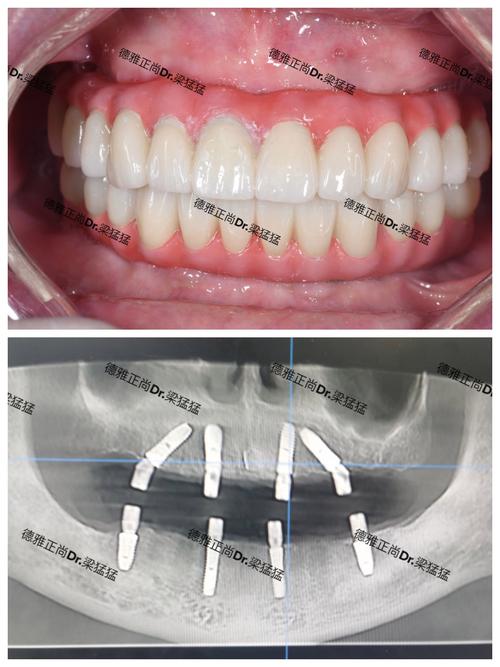

- 影像学检查: 拍摄根尖片或CBCT,评估种植体的位置、角度、牙冠边缘的密合度、牙槽骨状况(尤其是邻牙区域)。